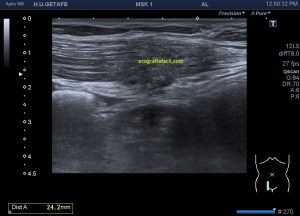

Durante la exploración de una eco de abdomen en el contexto de un paciente que acude por elevación de transaminasas observo una imagen heterogénea, irregular, con una pared marcadamente calcificada, bilobulada de gran tamaño que medí en dos partes ya que me pareció claramente que estaban diferenciadas.

Una de ellas, la primera, era mucho más hiperecogénica y más pequeña, su centro estaba mas calcificado, su sombra acústica posterior era mucho más acuciada y llamaba más la atención. Justo al lado, otra lesión de mayor tamaño, su calcificación era mucho más sutil y más periférica delimitando una LOE hipoecogénica de un tamaño muy importante, adyacente a la más pequeña, como he comentado previamente. Ambas sin señal Doppler.